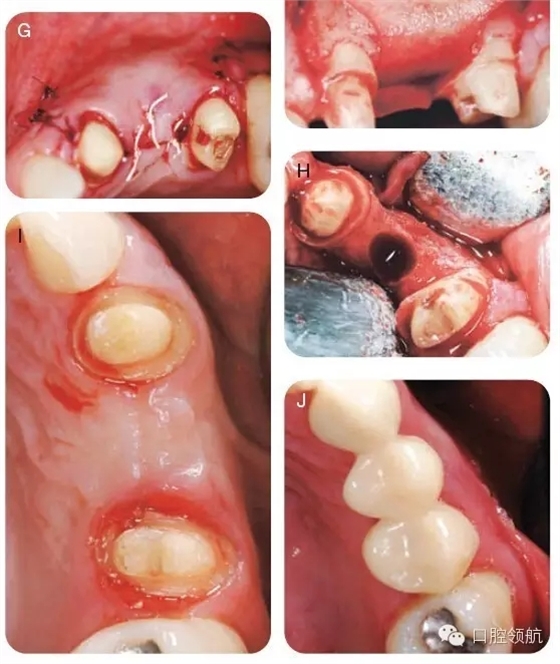

用2%利多卡因(1/100000腎上腺素)行下牙槽后、中神經(jīng),腭大神經(jīng)阻滯麻醉,局部浸潤(rùn)麻醉。附加兩個(gè)垂直方向的松弛切口使得視野更加清晰并減低術(shù)后瓣撕裂的可能,上頜右側(cè)1/4區(qū)域翻開(kāi)全厚瓣以充分暴露骨皮質(zhì)(圖6A~C)。暴露術(shù)區(qū),用圓形金剛鉆去除該區(qū)的骨皮質(zhì),使得術(shù)區(qū)有血液流出。打入兩個(gè)10mm的支帳螺絲并且確認(rèn)其穩(wěn)定(圖6D)。取稍過(guò)量的脫礦凍干骨置于該區(qū)域(圖6E)。放置堅(jiān)固的可吸收膠原膜( O s s e o g u a r d -Collagen Matrix, Inc, Franklin Lakes,NJ, USA)于移植物上(圖6F),復(fù)位瓣并原位縫合。組織愈合良好(圖6G)。在GBR術(shù)后6個(gè)月,再次麻醉并暴露術(shù)區(qū),制備直徑為4.1mm的植入位點(diǎn),使得頰舌側(cè)有足夠的余留骨,以確保組織的長(zhǎng)期穩(wěn)定性并防止組織退縮(圖6H),在最終固定冠修復(fù)前,拍攝照片,顯示牙槽骨寬度顯著改善(圖6I,J),圖7為最終修復(fù)當(dāng)日照片。

圖6 (A~J)手術(shù)時(shí)的口內(nèi)照。

E. GBR包括一系列技術(shù),比如牙槽嵴保存術(shù),上頜竇提升術(shù),種植體周?chē)鶪BR,以及牙槽嵴提升術(shù)。這里主要討論牙槽嵴提升術(shù)。手術(shù)一般是從切除牙槽嵴頂?shù)慕腔M織開(kāi)始,頰舌側(cè)翻開(kāi)全厚瓣以充分暴露骨缺損區(qū)(圖5A,B)。在暴露的皮質(zhì)骨上打孔,即去皮質(zhì),使得自體骨中有骨生成能力的成分,比如血供、成骨細(xì)胞以及生長(zhǎng)因子進(jìn)入移植物中(圖5B),而后植入稍多量的異體骨以補(bǔ)償后續(xù)的吸收(圖5C),安放屏障膜,確保充分覆蓋于牙槽嵴頂(圖5D)。

為了達(dá)到術(shù)區(qū)的初期閉合,需要行松弛切口(圖5E),大多數(shù)建議應(yīng)在術(shù)后10~14天拆除縫線,且術(shù)后2~3周后不要行修復(fù)治療,以避免在早期愈合中對(duì)創(chuàng)口施壓。